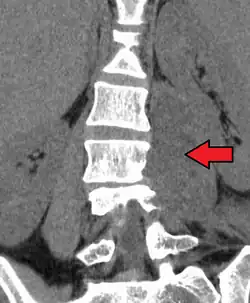

Psoas abscess

| Paraspinal abscess in the psoas muscle | |

Psoas abscess is a collection of pus (abscess) in the iliopsoas muscle compartment.[1][2][3] It can be classified into primary psoas abscess (caused by hematogenous or lymphatic spread of a pathogen) and secondary psoas abscess (resulting from contiguous spread from an adjacent infectious focus).[3]